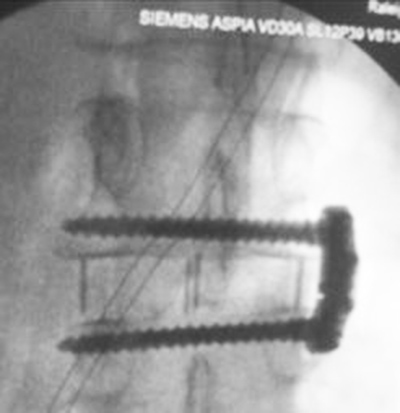

Extreme lateral interbody fusion (XLIF) is a minimally invasive surgical procedure performed from a lateral approach to remove a diseased disk with placement of an artificial disk and performance of lateral fixation with plate and screws going into the vertebral bodies above and below the diseased disk space level (Nuvasive) (Ha, 2014; Petscavage-Thomas, 2020) (figure: XLIF). A similar procedure is the transforaminal lumbar interbody fusion (TLIF).